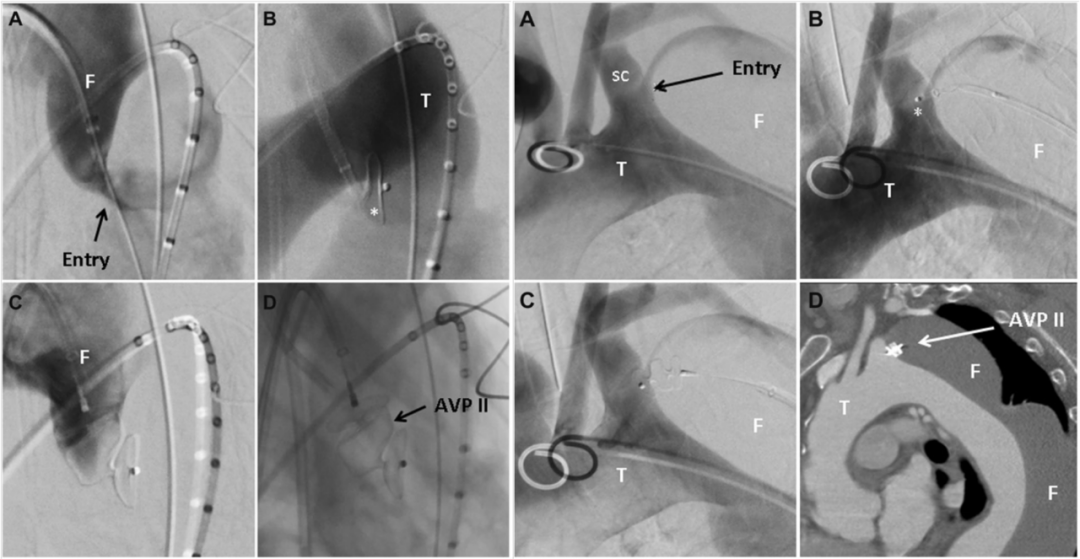

前瞻性的研究对于EVAR术前单侧或双侧栓塞ⅡA术后臀肌跛行发生情况进行比较,表明在术后6个月后臀肌跛行状况有所改善,但双侧髂内栓塞似乎比单侧栓塞更严重。因此,建议至少保留一侧ⅡA。对于术后对运动要求不高的患者,盆腔血供更丰富,出现臀肌跛行的概率更低。而轻微臀部跛行并不会影响患者生活质量。而对运动、性生活需求高的患者,也可通过三明治、IBD/IBE、带分支支架等方法进行髂内重建。2016年,Falkenberg等提出一种新的血管内技术——主动脉夹层裂口栓塞技术,以避免部分因主动脉弓慢性小夹层破口导致动脉瘤扩张的患者中进行开放手术重建。技术特点是使用AVP Ⅱ从假腔侧通过近端破口推进,作为破口孔内的密封按钮展开,使得AVP Ⅱ的1个瓣在真腔内,其余2个瓣在假腔内。该技术应用于4例累及主动脉弓的慢性夹层患者,其中3例成功栓塞了胸主动脉假腔,随访期间血栓形成和主动脉内径缩小。由此可见,采用AVP Ⅱ作为封闭按钮对主动脉弓近端小夹层破口进行血管内封闭是可行的,在选定的慢性主动脉弓夹层和继发性动脉瘤扩张患者中,可能是开放手术重建弓的替代方案。

2007~2016年间的14例扩张性慢性主动脉夹层患者(被认为不适合标准治疗)接受了位于主动脉弓(n=6)或降主动脉(n=8)近端破口的腔内血管塞栓塞治疗。其中10例(71%)患者实现了近端破口的栓塞。并在所有10例成功栓塞的患者中,观察到胸主动脉最大直径减小。扩张性慢性主动脉夹层近端夹层破口的腔内栓塞可诱导良好的主动脉重构。对于不适合开放修复或TEVAR的扩张性慢性主动脉夹层患者,采用腔内血管塞栓塞近端破口是一种微创和安全的选择。

病例1为72岁的男子曾因AAA接受治疗,被诊断为70 mm的Ⅲb型主动脉夹层。使用Amplatzer血管塞封闭了5 mm内膜破口,成功修复。患者顺利出院,无并发症,随访CT显示,血管塞无移位,主动脉直径变小。

病例2为75岁女性因Stanford A型主动脉夹层行紧急升主动脉置换手术,残留降主动脉破口。使用AVP Ⅱ顺利栓塞破口,随访影像显示假腔血栓化。

病例3为79岁男性,患者有DeBakey Ⅰ型主动脉夹层。患者不耐受开放手术,使用AVP栓塞近端破口,顺利实现封堵。随访CT显示假腔血栓化。

综上所述,现有应用AVP栓塞主动脉夹层裂口的病例报告表明了该技术的可行性和有效性。该技术操作简便易行,疗效显著,是否常规应用取决于病变本身特点,包括解剖学条件,患者的自身情况、裂口大小等。后期还需要大规模前瞻性研究以改写或增补指南。